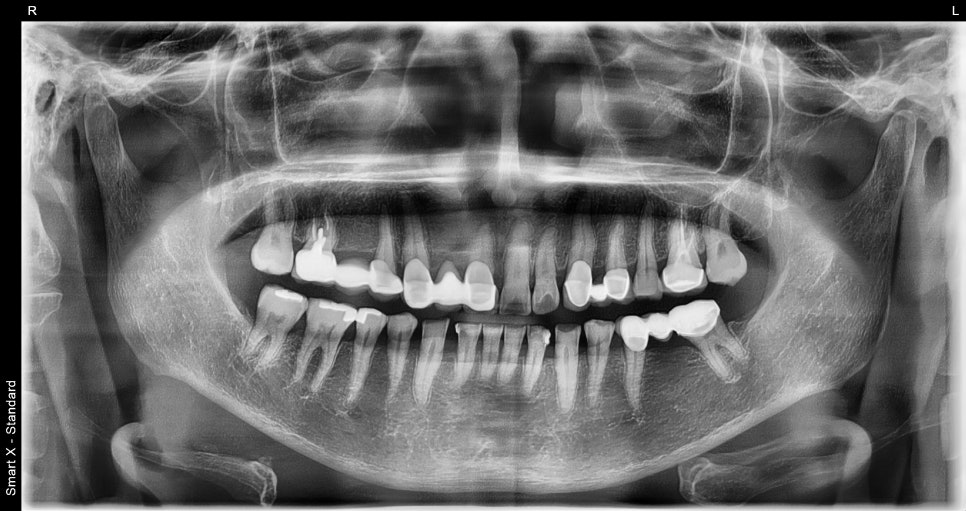

Panoramic X-ray at the first visit

➤ Initial examination findings

Before planning the aesthetic front tooth prosthetics and molar implant treatment, here is the patient's initial condition.

After a comprehensive diagnosis of tooth alignment, missing areas, and the condition of existing prosthetics, the following treatment plan was explained:

Right lower molar area (#45~47): We recommended removing the old bridge and making new crowns for #45 and #47, and for the empty space at #46, we recommended placing one implant instead of the existing bridge.

Front tooth area (#11): There was severe cervical wear, and additional prosthetic treatment was needed.

Lower front tooth area (#43, #42): The space between the teeth had widened, so we planned an aesthetic improvement using crowns.